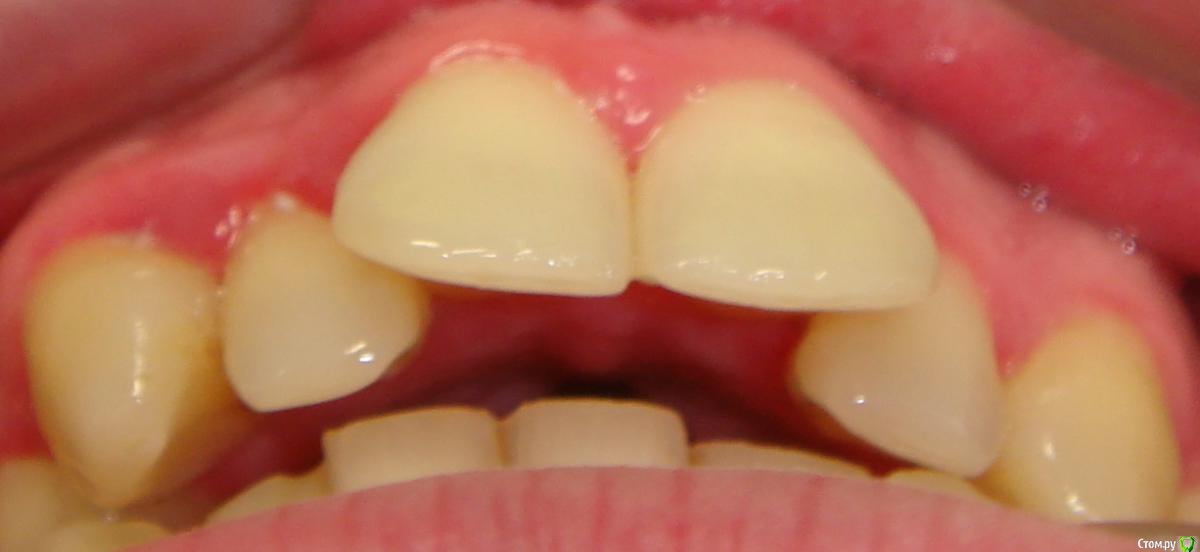

Здравствуйте, Коллеги. Вот такой вот случай, пациент 32 года. Изначально, хотел дистализировать в первом сегменте с целью апрайтинга 13 - 16, провести апрайтинг боковых зубов н/ч, затем САРПЕ и MEAW, понятно, что восьмерки долой еще до лечения. Но потом увидел форму корней 37, 47 (это не искажение, по КТ они и правда такие) и кисты прорезывания за ними. В связи с этим мне кажется, что апрайтинг снизу невозможен, так как эти верхушки никуда меня не пустят, разве что ввиду проблем с пародонтом семерки тоже уйдут. Вопрос: что делать??? Даже если отбросить мультилуп и готовить его на ортогнатию, то апрайт все-равно нужен, как поступить? Заранее спасибо!

P.S.: Забыл... сверху семерки такие же.